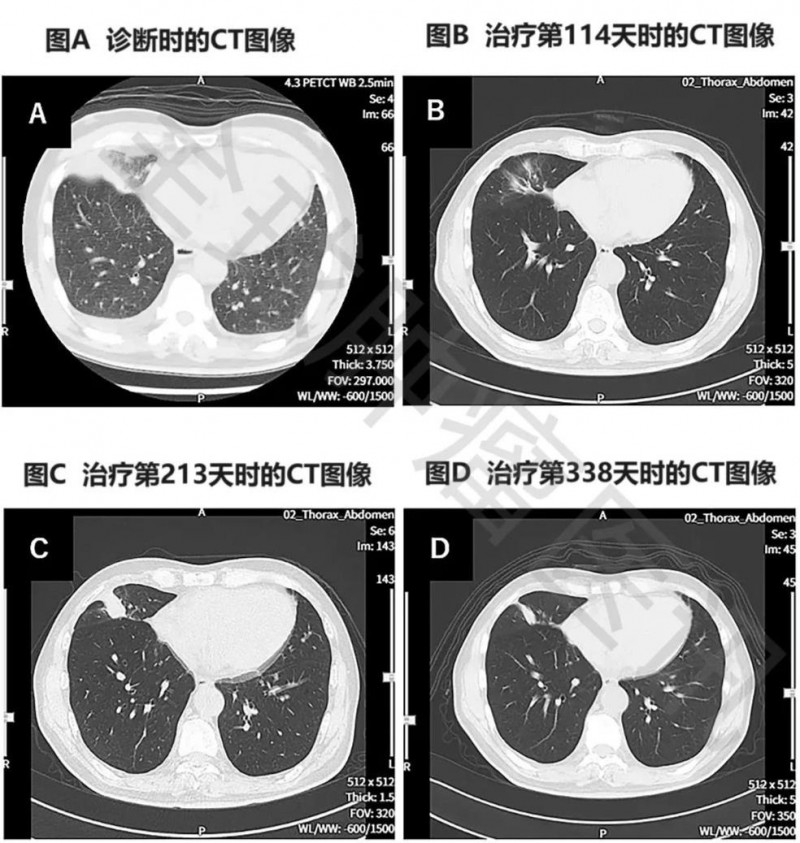

3、胸部CT显示:该患者在治疗第114天,复查胸部CT显示,肿瘤明显缩小(详见图2)。

图 治疗前后胸部CT图像对比

①图A示:原发性右下肺癌,同时伴左右胸腔积液。

②图B示:原发病灶几乎消失。

③图C示:原发病灶存在一定程度的复发。

④图D示:原发性及复发性病灶均缩小。